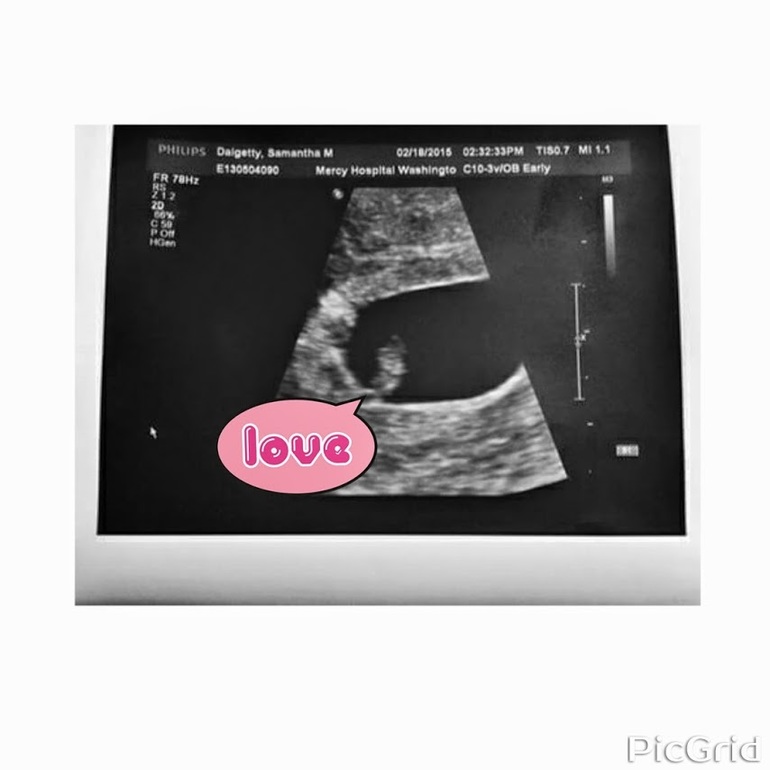

Наши будни, наши неделькиВ пятницу (20.02) состоялась наша первая встреча с кнопочкой (а также горошинкой, бусинкой, креветочкой - кто как называет

). Срок - 5+3 недель.

Итак, в матке один эмбрион со стучащим

(149 уд\мин); КТР - 3,5 мм:) Мы еще очень-очень маленькие:) На УЗИ торопилась, так как в первую беременность на этом сроке я уже лежала в больнице с гипертонусом и угрозой выкидыша - очень боялась повторения; но врач заверила, что тонус матки нормальный и что ничего, кроме моей излишней нервозности, нашей крошке не угрожает. Прямо в кабинете врача дала себе слово беречь нервы, ради малыша - пока держусь